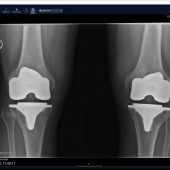

München – Der letzte Ausweg aus der Arthrosefalle kann auch eine große Chance sein: Allein in Deutschland lassen sich jedes Jahr mehrere... zum Artikel

Der 67-jährige Wolfgang Klaus aus dem Landkreis Freising macht Arthrose-Leidensgenossen Mut Langenbach – Niemand legt sich gerne unters Messer. Aber manchmal kommt man um die OP nicht mehr herum. So wie Wolfgang Klaus aus Langenbach im Kreis... zum Artikel

Eine Gelenkersatz-OP muss nicht zwingend immer unter Vollnarkose vorgenommen werden. Sowohl künstliche Knie als auch Hüften lassen sich auch unter Teilnarkose einsetzen. Bei der sogenannten Spinalanästhesie wird nur die untere Körperhälfte betäubt,... zum Artikel

Wie kann man den Gelenkersatz noch sicherer machen? Daran feilen die Spezialisten auch mithilfe modernster Technik. So wird im Uniklinikum rechts der Isar ein OP-Roboter genutzt. „Er unterstützt uns Ärzte beim Einsetzen von künstlichen Knien“, sagt... zum Artikel